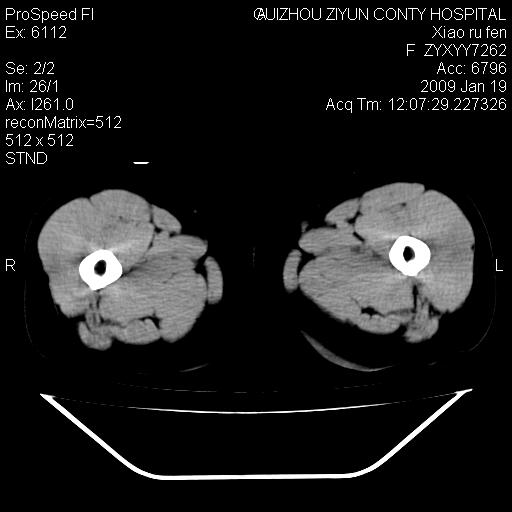

以下是引用随光逐影在2009-1-19 16:15:00的发言:[br]左侧臀部类似软组织密度肿块,性质待定(不排除肿瘤可能);建议行进一步检查。

以下是引用zbp537在2009-1-19 14:25:00的发言:[br]考虑两个诊断:1、皮脂腺囊肿伴感染。2、脓肿。[br]诊断依据:[br]1、肿块为低密度,边界较清,和皮肤相连,周围结构清晰,未见受累及。[br]2、诊断脓肿是因为其内密度不均匀,当然要结合病史,因为脓肿临床上肯定表现为红肿热痛,也希望楼主把病史提供全面些,这些便于讨论。

以下是引用zbp537在2009-1-19 14:25:00的发言:[br]考虑两个诊断:1、皮脂腺囊肿。2、脓肿。[br]诊断依据:[br]1、肿块为低密度,边界较清,和皮肤相连,周围结构清晰,未见受累及。[br]2、诊断脓肿是因为其内密度不均匀,当然要结合病史,因为脓肿临床上肯定表现为红肿热痛,也希望楼主把病史提供全面些,这些便于讨论。